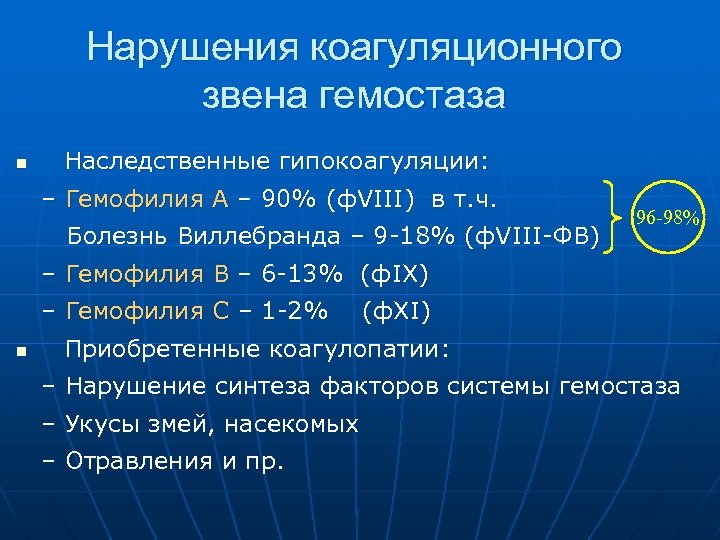

Нарушения коагуляционного звена гемостаза n Наследственные гипокоагуляции: – Гемофилия А – 90% (ф. VIII) в т. ч. Болезнь Виллебранда – 9 -18% (ф. VIII-ФВ) 96 -98% – Гемофилия B – 6 -13% (ф. IX) – Гемофилия С – 1 -2% n (ф. XI) Приобретенные коагулопатии: – Нарушение синтеза факторов системы гемостаза – Укусы змей, насекомых – Отравления и пр.